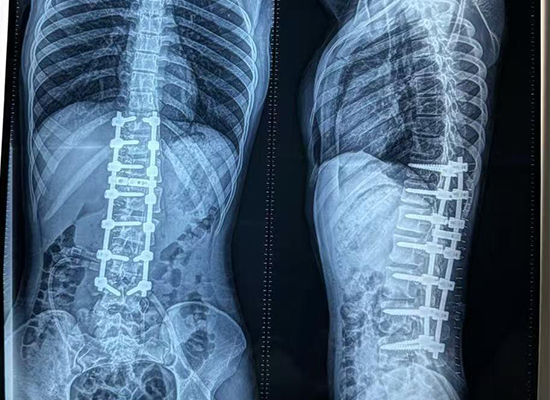

Preoperative imaging showed:

Marked lateral curvature of the thoracolumbar spine

Vertebral rotation and rib prominence

Imbalanced shoulders and trunk alignment

These findings confirmed the need for posterior spinal deformity correction and fusion using a pedicle screw–rod construct.

Preoperative full-spine X-ray showing thoracolumbar scoliosis in a 16-year-old patient from Dhaka, Bangladesh.

Postoperative imaging demonstrated:

Significant improvement in spinal alignment

Reduced curvature and rib prominence

Balanced shoulders and trunk